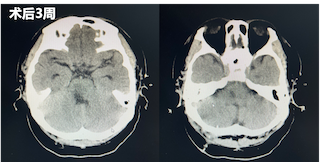

术后第一天,患者仍为浅昏迷状态,但在刺激下可见患者四肢收缩,复查头部CT发现脑干血肿较前明显减少。经神经内科重症监护室医护人员为其制定了专业的诊疗计划,随后团队成员持续术后关注,并向穿刺引流管中注射溶解血肿块的药物。随后,患者逐渐有了意识,对于外界的呼唤有了反应,对外界的刺激产生了回应。

术后一周再次复查CT显示脑干中的血肿明显较前减少。直至三周后,再次复查CT,患者已经没有血肿块,意识较前明显好转,遂转入普通病房继续治疗。在普通病房,患者还同时接受专业的康复训练和中医针灸治疗,患者四肢活动较前好转,目前,已出院至康复医院继续进行康复训练。